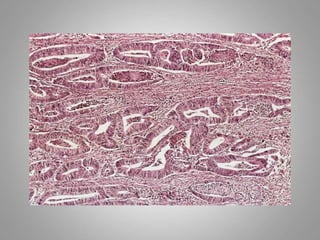

– Adenoma : benign epithelial neoplasms producing

gland pattern….OR … derived from glands but not

necessarily exhibiting gland pattern

Adenocarcinoma: One with a glandular growth

pattern microscopically.

Adenocarcinoma

Adenocarcinoma: One with a glandular

growth pattern microscopically.

Malignant neoplasm ofepithelial cells origin derived from any of the three germ layer , are called Carcinomas. Cell of origin + Carcinoma Squamous cells + carcinoma = squamous cell carcinoma Adenocarcinoma: One with a glandular growth pattern microscopically.

Adenocarcinoma: One witha glandular growth pattern microscopically.